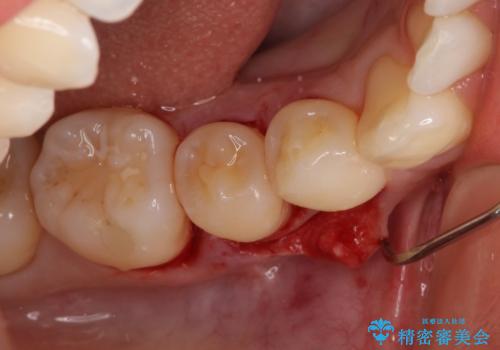

患者様は、他院で右下の歯を抜歯かもと言われました。全体の歯周病はなく、右下の1歯だけ骨が極端に減少していました(初診時歯周ポケット7mm。通常は3mm以下。)。その歯だけ咬合が強いことが原因と考えられたため、咬合を弱くする処置と減少した骨を再生する処置が必要になりました。

骨の再生治療手術をして10か月経過観察をしたのち、骨を平坦化する手術を行い、治療終了となりました。